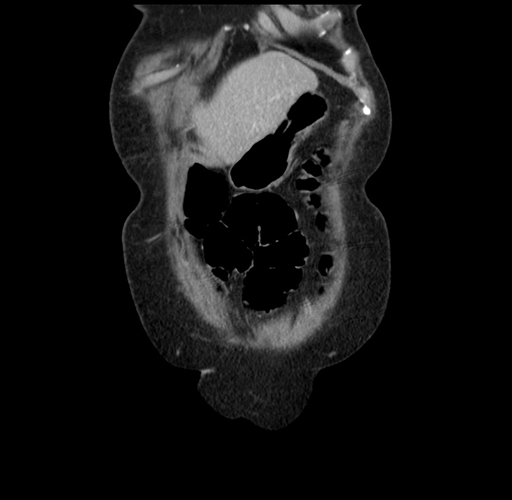

MRI T1